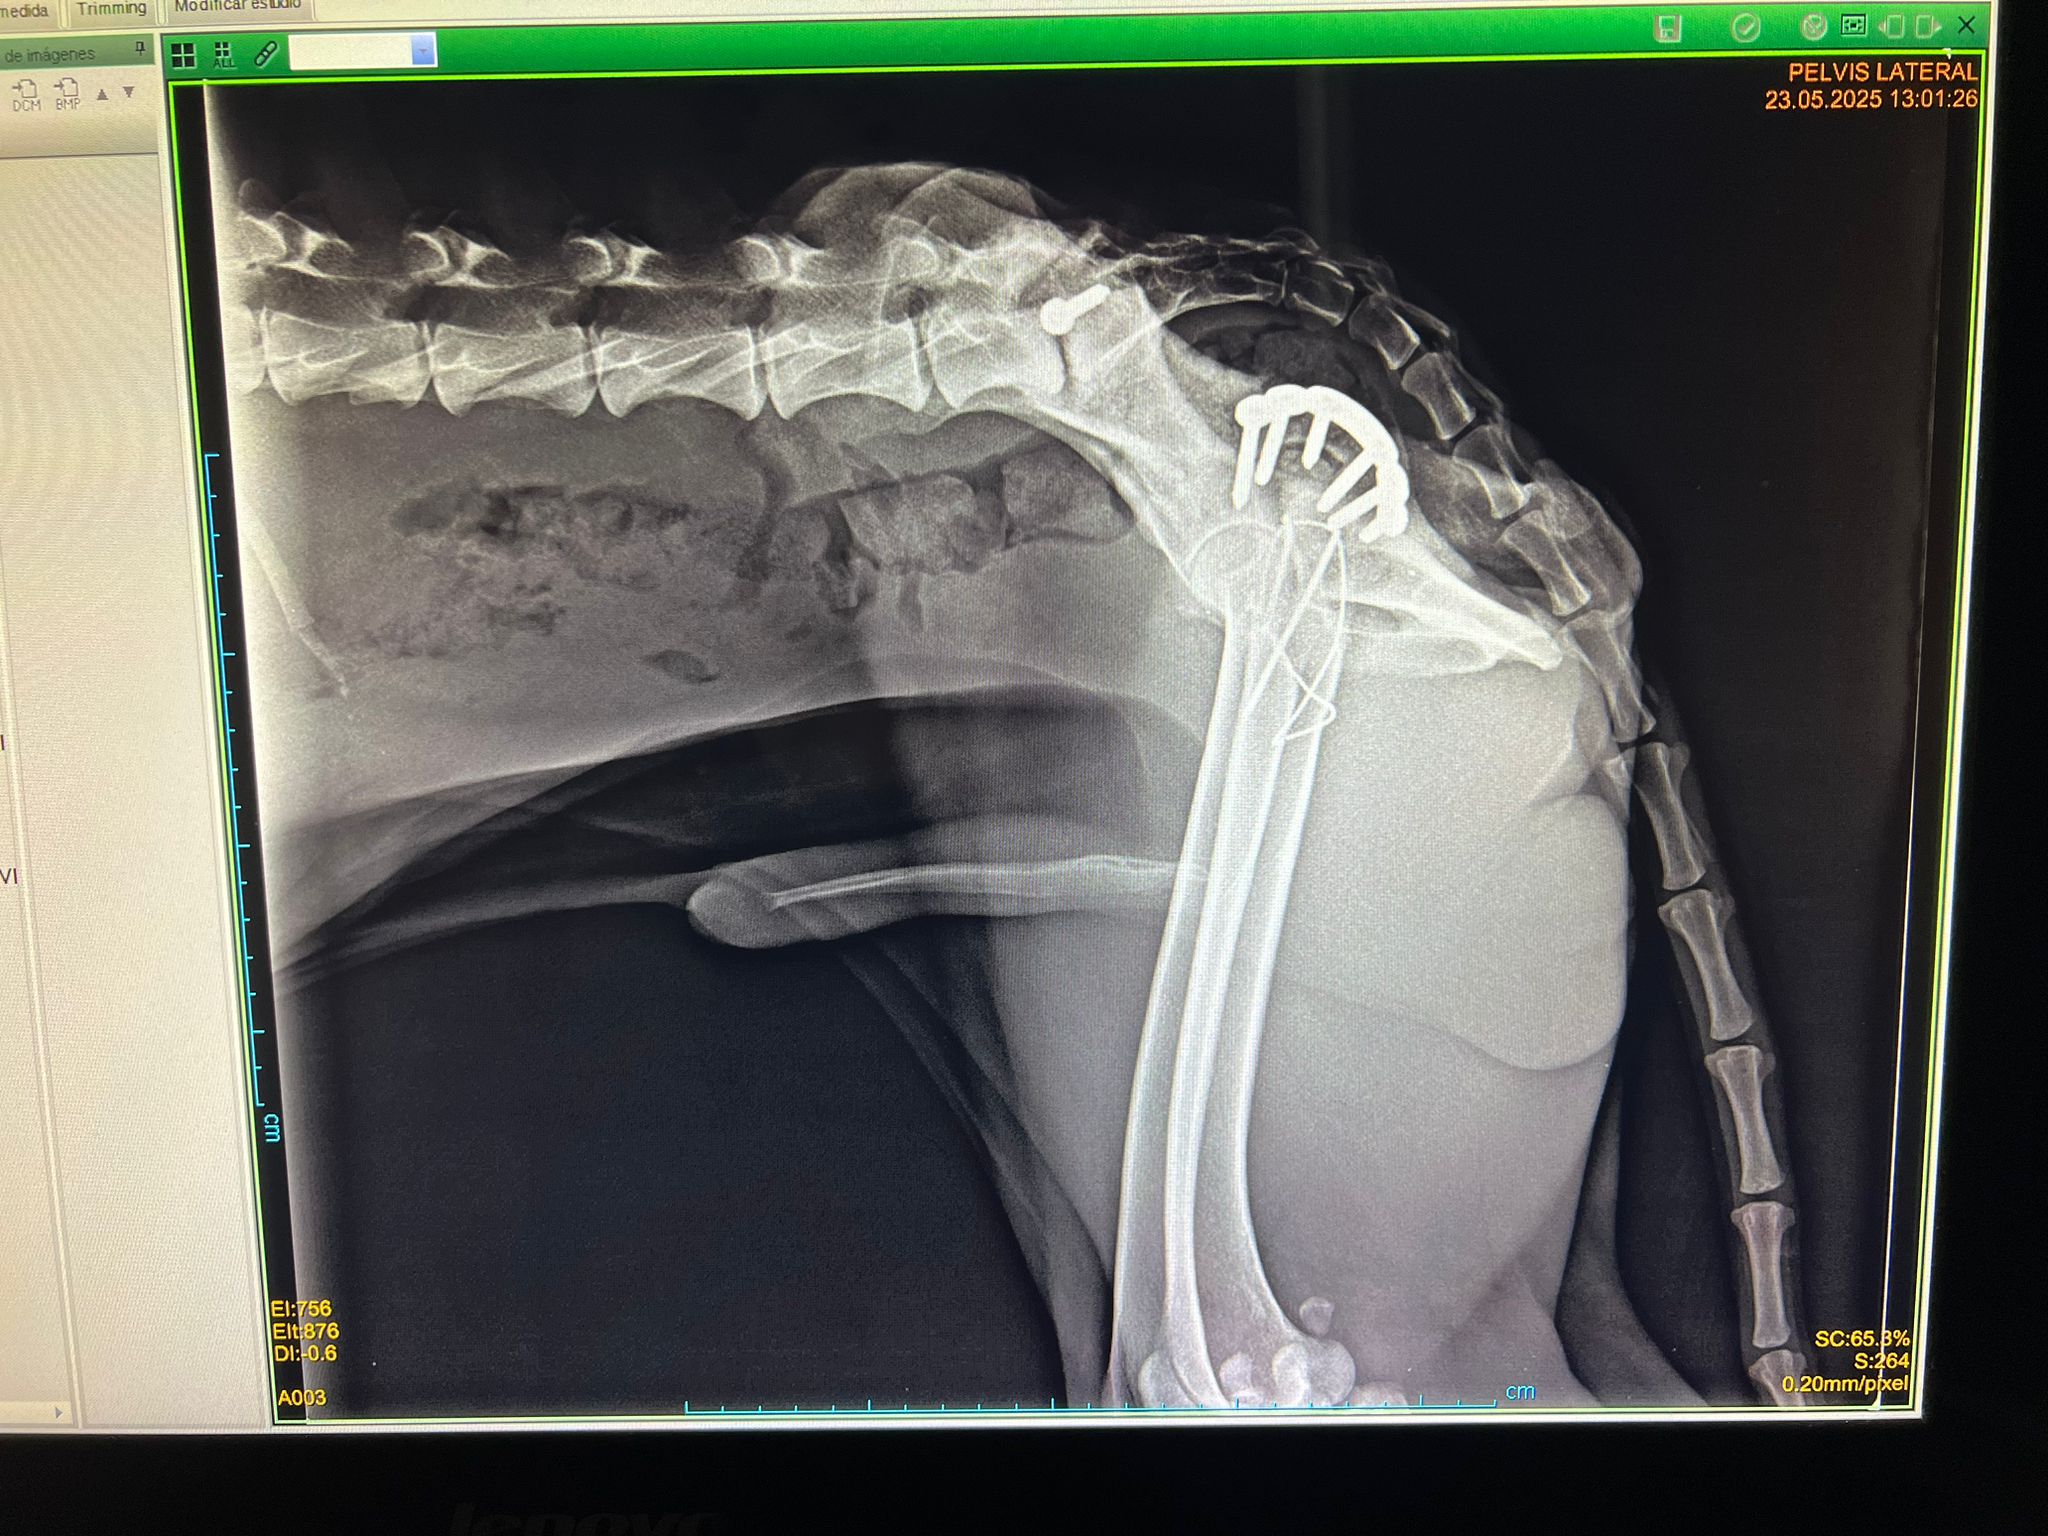

Lucio fue adoptado de un centro de recogida de Toledo. Cuando llegó, estaba muy delgado y tenía dos fracturas por un recogieron atropellado. Ya lo operaron de estas fracturas y se encuentra muy bien.

Lucio was taken over from another rescue in Toleda. When Lucio arrived, he was very skinny and had two fractures because he was hit by a car. He’s been operated on these fractures and is doing very well.